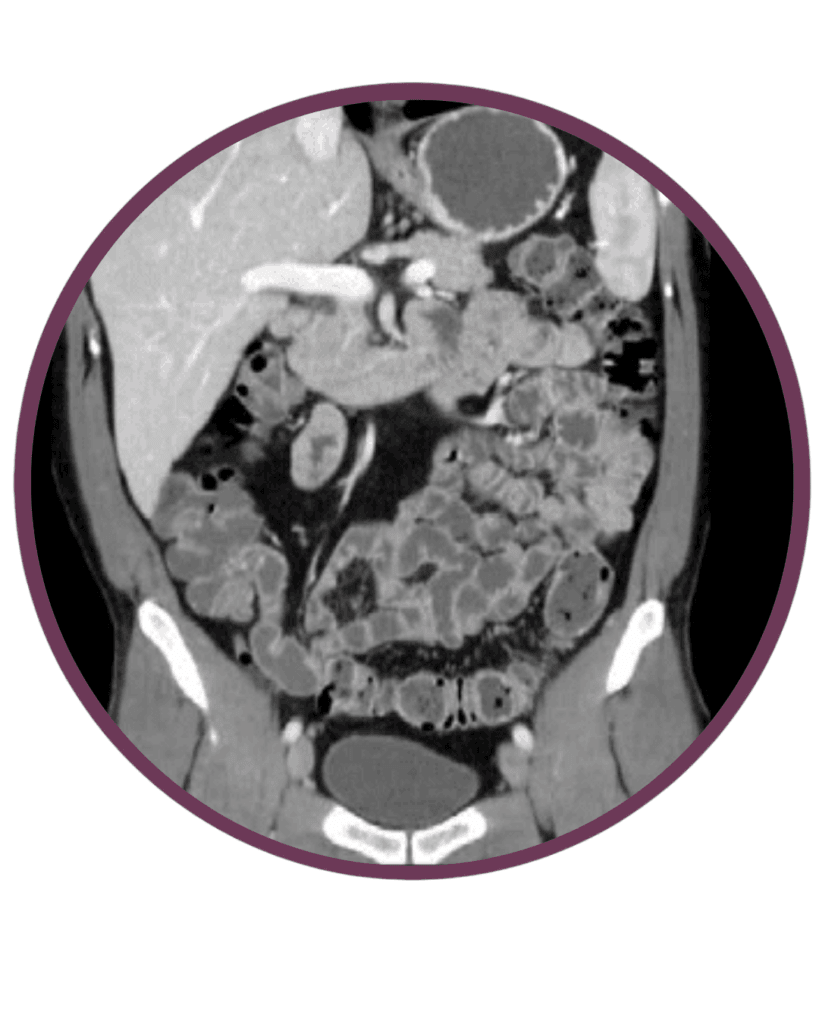

Has és kismedence natív és kontrasztos CT

A CT vizsgálat alapvető jelentőségű diagnosztikus eljárás a teljes hasüregben lévő (pl.: máj, epeutak, hasnyálmirigy) gyulladásos elváltozásai, illetve daganatos betegségek gyanúja vagy már szövettanilag igazolt daganatos kórképek kiterjedésének és esetleges áttétképződésének kimutatásában.  A vizsgálat nagy pontossággal kimutatja az elsődleges (primer) daganatos folyamat kiterjedését, környezethez való viszonyát, a daganat esetleges környező (lokoregionális) nyirokcsomókba terjedését és a távoli áttétek jelenlétét. A CT vizsgálatot alkalmazhatjuk a műtéti kezelés kivitelezhetőségének (operabilitás) megítélésére, valamint a sikeres műtéti és onkológiai (daganatgátló gyógyszeres és sugárkezelés) terápiát követően a betegség teljes gyógyulásának (teljes remisszió), részleges gyógyulásának (részleges remisszió) vagy változásának (progressió) megítélésére és fél vagy évenkénti utánkövetésére.